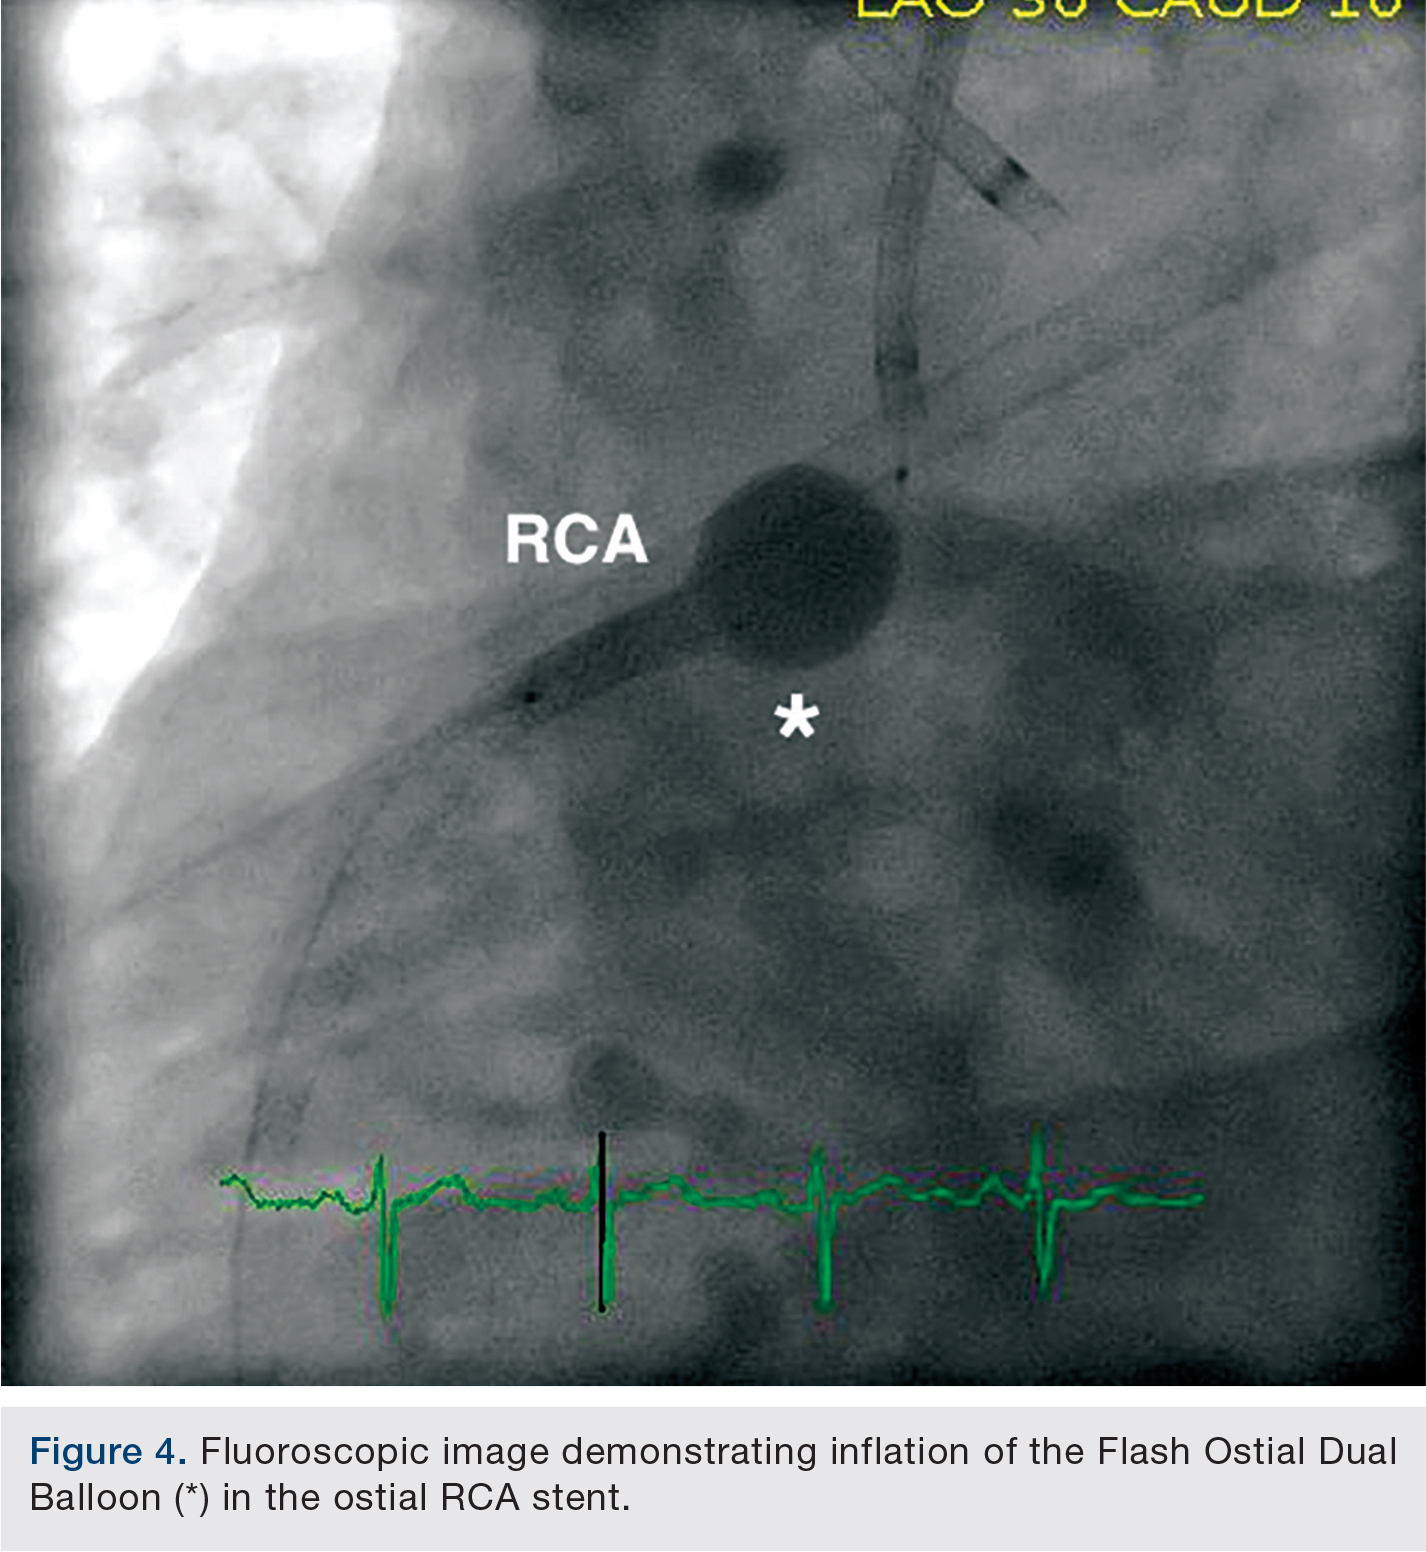

A short ostial 4.0 x 16mm Promus Premier stent (Boston Scientific) was deployed with 1-2mm extending into the aorta. A 4.0 x 14mm Flash Ostial Dual Balloon coronary angioplasty catheter (AccessClosure) was then inflated in two sequential maneuvers: first, the elongated body of the non-compliant balloon was inflated to 14 atmospheres, and second, the spherical flash ostial portion of the balloon was inflated with 0.9cc of contrast medium for a total of 3 seconds in order to flare the ostial stent margin to the aorta (Figure 4). The final RCA angiogram revealed brisk antegrade flow and an appropriately flared ostial stent margin well apposed to the aortic wall (Figure 5). The patient’s femoral arteries were sealed with 8 French Angio-Seal (St. Jude Medical) vascular closure devices and the patient was discharged the following day in stable condition after being loaded with dual antiplatelet therapy.